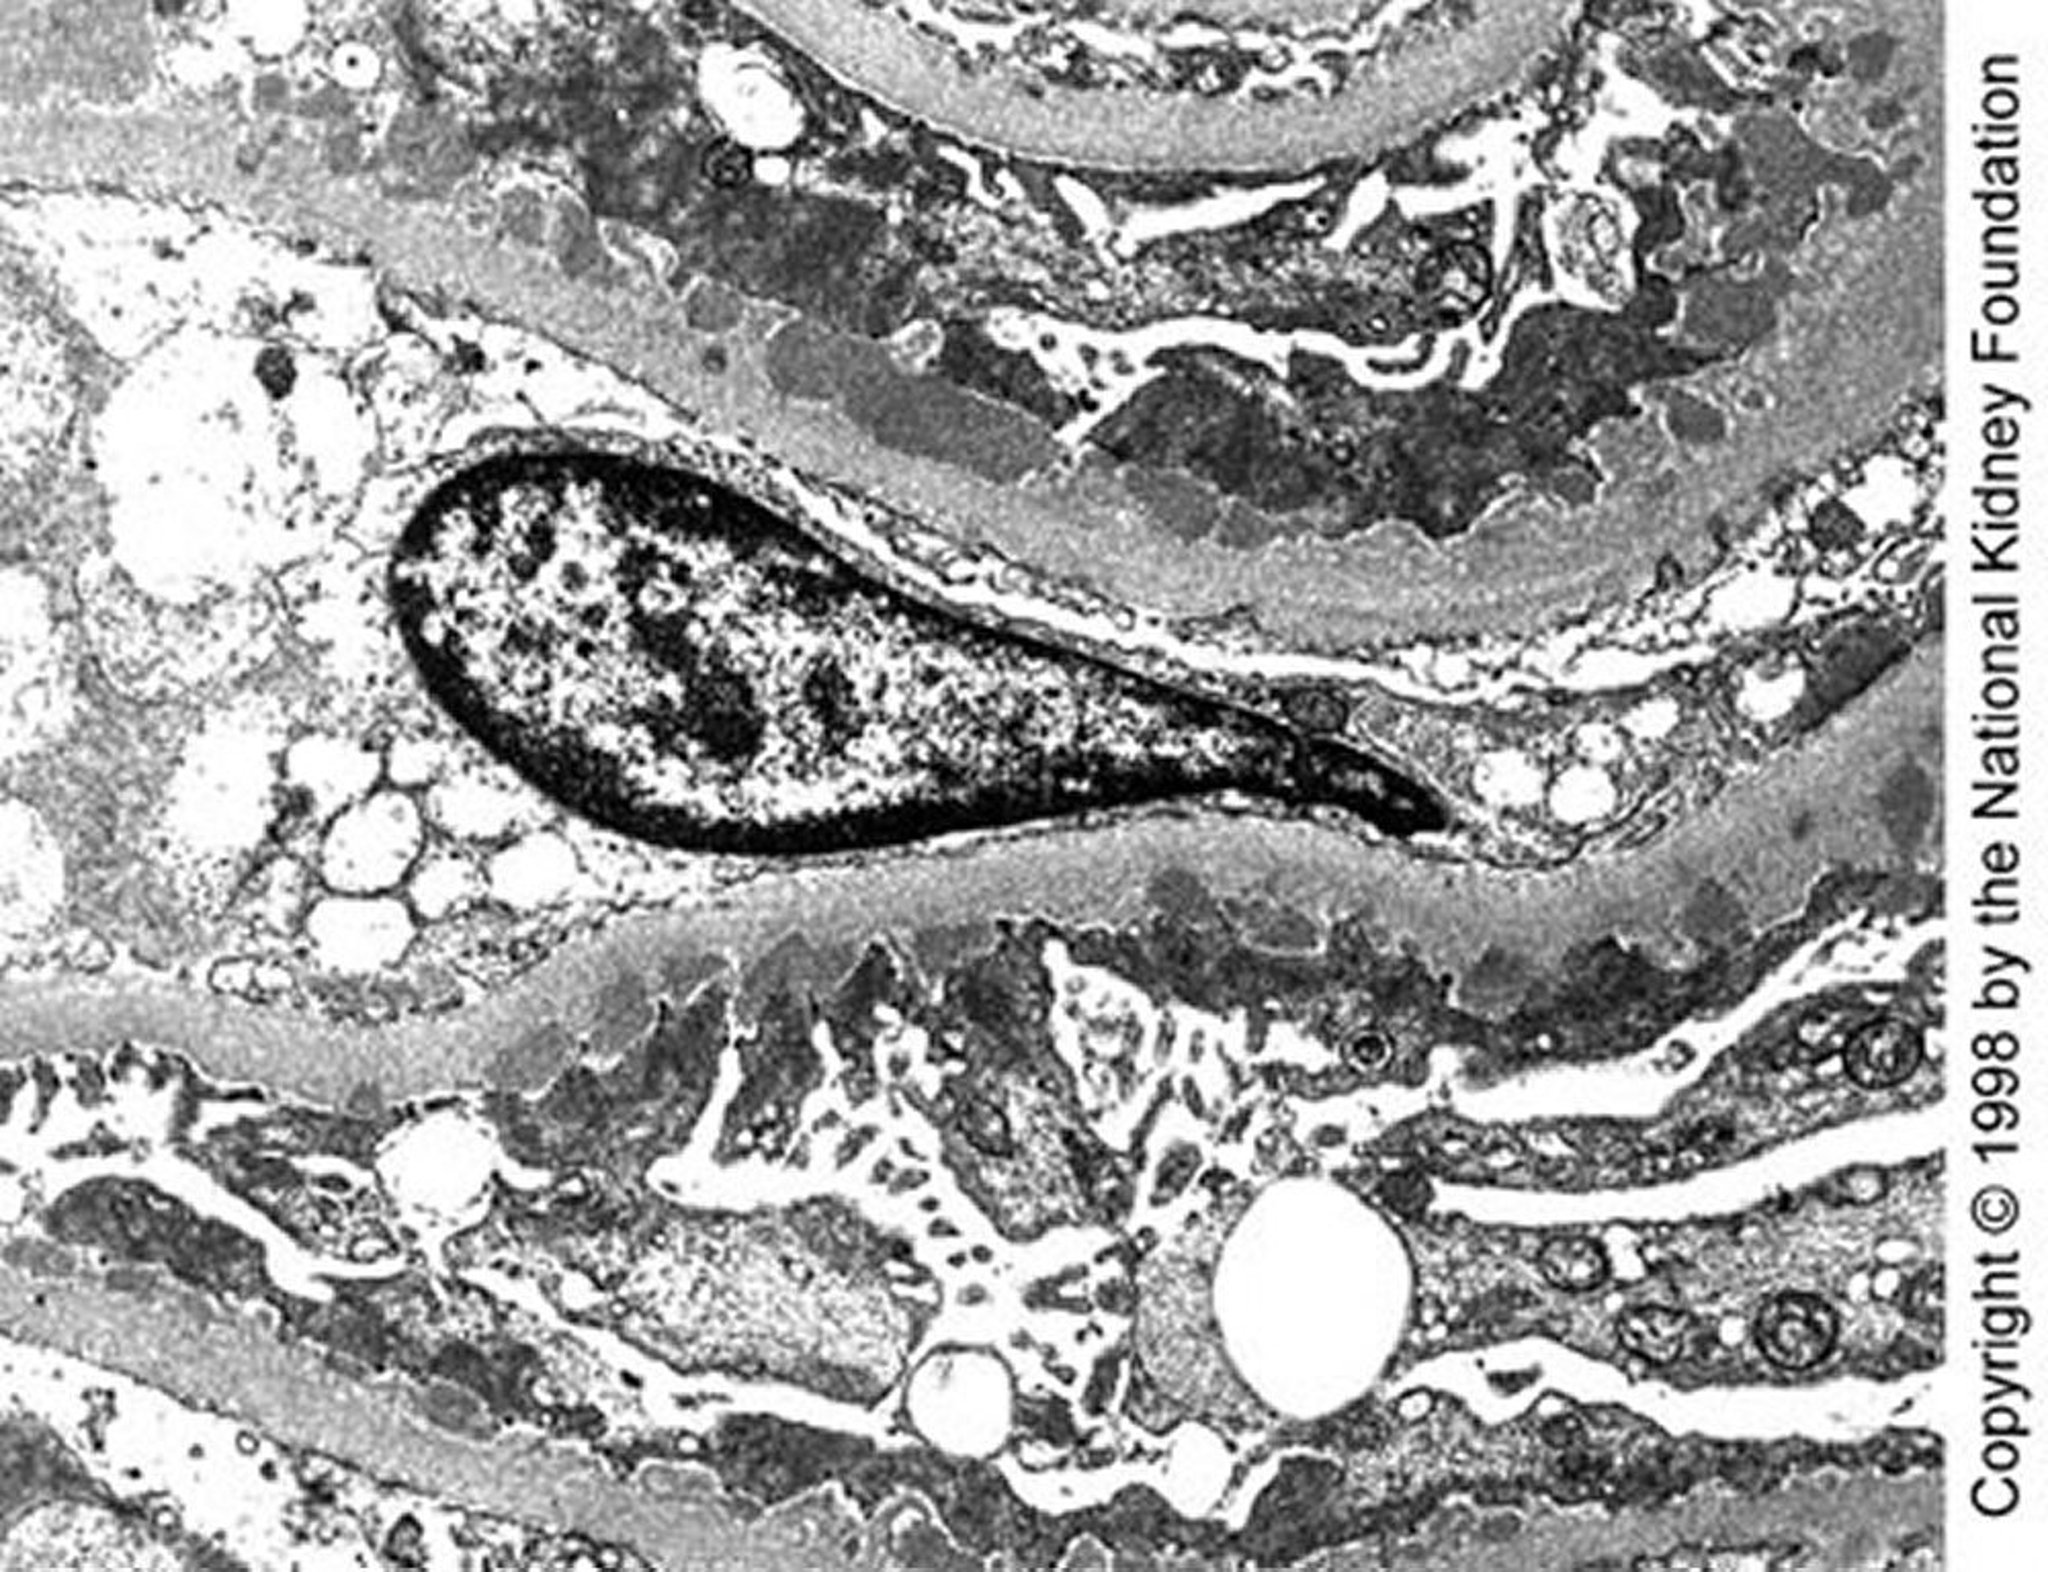

Bệnh thận màng (lắng đọng dày đặc)

Các chất lắng đọng dày đặc dưới biểu mô có kích thước trung bình được quan sát thấy trên kính hiển vi điện tử truyền qua trong bệnh giai đoạn I muộn (×10.200).

Hình ảnh do bác sĩ Agnes Fogo và American Journal of Kidney Diseases' Atlas of Renal Pathology cung cấp (xem www.ajkd.org).